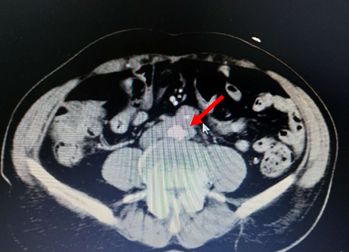

腹部CT检查结果如下:

考虑慢性胰腺炎,脾静脉血栓形成,伴脾门及胃周多发侧枝血管形成,同时合并腹主动脉夹层ⅢB型(Debakey分型),立即严格控制血压在120/80 mmHg一下,同时内科止血、输血后HGB达97 g/L转外科进一步治疗(脾切除术+胃周血管离断术以及腹主动脉支架植入术)。